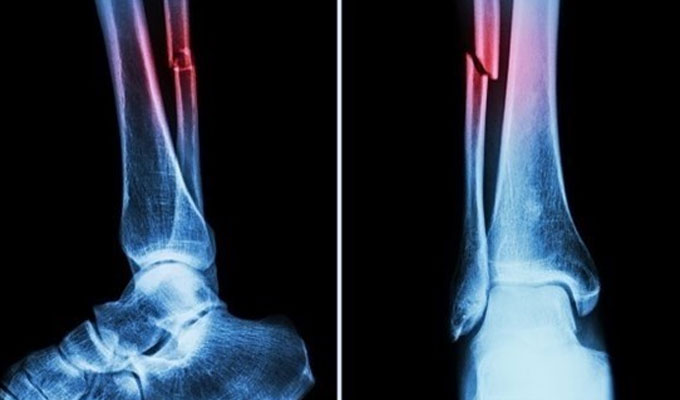

צוות מחקר במחוז ג’ג’יאנג במזרח סין הכריז על מוצר רפואי חדש: “דבק עצם” המסוגל לטפל בשברים ולחבר מחדש שברי עצם תוך שלוש דקות בלבד, במהלך המתואר כפריצת דרך מדעית בעולם הכירורגיה האורתופדית, על פי NDTV .

בדיקות מעבדה אישרו כי Bone-02 השיג תוצאות טובות מבחינת בטיחות ויעילות. בניסוי אחד, ההליך בוצע בפחות מ-180 שניות (שלוש דקות), בעוד ששיטות טיפול מסורתיות דרשו זמן רב להשתלת לוחות פלדה וברגים.

על פי בדיקות מעבדה, הדבק הצליח להשיג חוזק הדבקה של יותר מ-400 פאונד, חוזק גזירה של כ-0.5 מגה-פסקל וחוזק דחיסה של כמעט 10 מגה-פסקל. ניסויים שנערכו ביותר מ-150 חולים הראו תוצאות מוצלחות, מה שמעלים את האפשרות שהוא יכול להפוך לחלופה לשתלי מתכת מסורתיים המשמשים לייצוב עצמות. מדענים אומרים שהוא עשוי גם להפחית את הסיכון לזיהום.